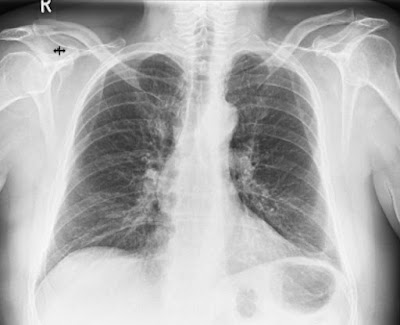

Da zeitweilig der Verdacht im Raum stand, ich könnte mir eine

LungenentzĂŒndung eingehandelt haben, wurde unter anderem

meine Lunge geröntgt

Zu meiner Erleichterung bestÀtigte sich der Anfangsverdacht nicht